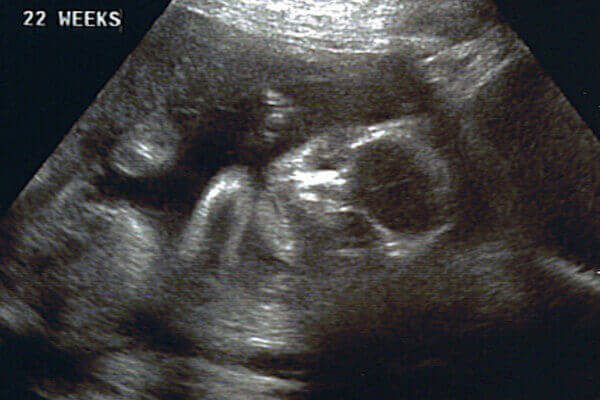

Що показує УЗД

На 22 тижні вагітності УЗД дозволяє виявити можливі проблеми в розвитку плода. Це дуже важливий термін для скринінгової діагностики, яка дозволяє:

- досліджувати стан навколоплідних вод, плаценти;

- виявити можливі вади розвитку.

На даний момент немає доказів і наукових пояснень того, що УЗД шкідливо для малюка. За весь період виношування вагітності припадає три планових дослідження. У 22 тиждень вагітності за допомогою УЗД можна отримати фото вашої дитини і виявити такі показники:

- довжина стегна;

- біпаріетальний розмір голови;

- куприко-тім’яний розмір;

- зростання плоду.